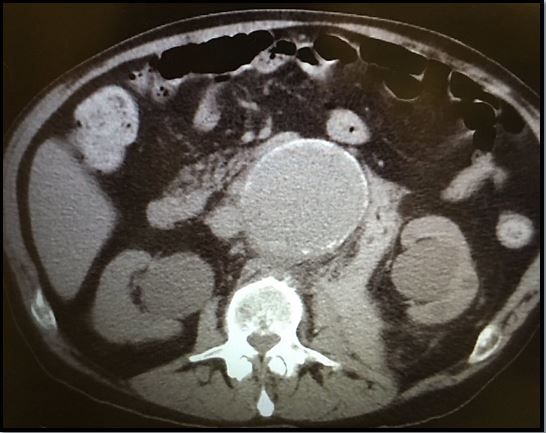

Answer. An abdominal aortic aneurysm (AAA). The CT scan (Figure 1) shows a 9- x 8-cm ruptured infrarenal AAA with retroperitoneal hemorrhage. Bilateral renal cysts are noted incidentally.

Ruptured or leaking AAA typically presents with back, flank, and/or upper abdominal pain. Syncope or near syncope may also occur. It can mimic many other conditions, such as renal colic, lumbar strain, and a variety of other conditions (see page shot in Figure 2 at right) AAA can also be asymptomatic; detection at this stage has a better prognosis.